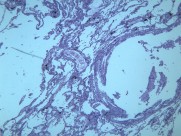

慢性支气管炎(chronic bronchitis)是由于感染或非感染因素引起气管、支气管粘膜及其周围组织的慢性非特异性炎症。其病理特点是支气管腺体增生、粘液分泌增多。临床出现有连续两年以上,每持续三个月以上的咳嗽、咳痰或气喘等症状。早期症状轻微,多在冬季发作,春暖后缓解;晚期炎症加重,症状长年存在,不分季节。疾病进展又可并发阻塞性肺气肿、肺源性心脏病,严重影响劳动力和健康。